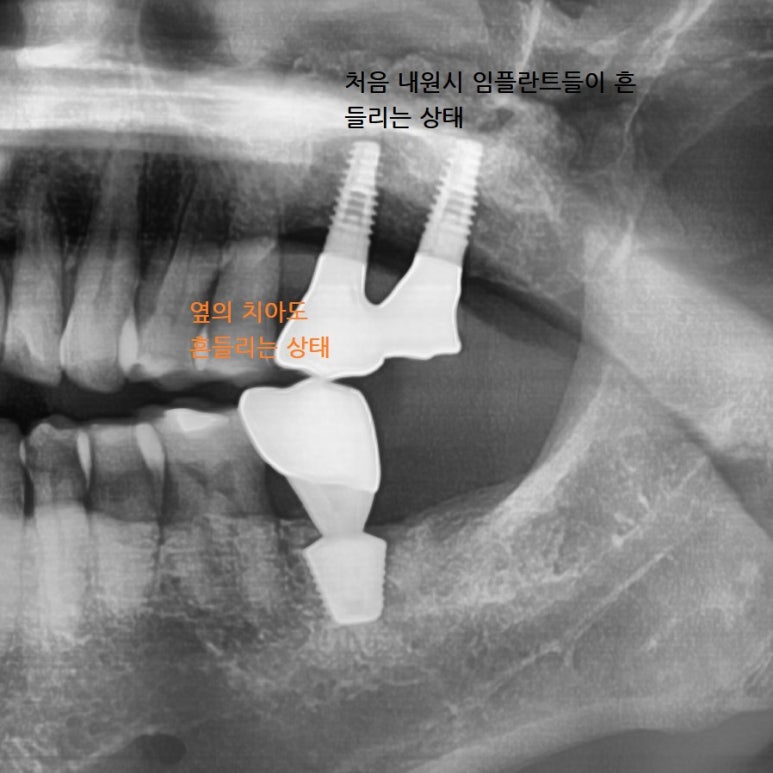

![[서울시청역치과] 다른 치과에서 오래전에 한 임플란트가 흔들려요 →재수술 케이스 관련 이미지 6](https://pub-9f2bb3498faf4d1d8714b41df24753e3.r2.dev/content/clinics/archive/rseeanjxfu/naver_blog/yonseiyegam/assets/by_hash/ea84db90f4b4850aa69afcafff7f723e6ab5ab76a91014b226204aea64acdc6b.jpg)

연결된 2개 인플란트 중

앞쪽 임플란트는 많이 흔들리는 상태였고 뒤쪽 임플란트도 반만 주변 뼈가 잡고있어 오래 못쓸거 같아

같이 빼기로 하였습니다.

또한 바로 앞의 치아도 많이 흔들려서 나중에 또 고생하느니 같이 발치하기로 하였습니다.